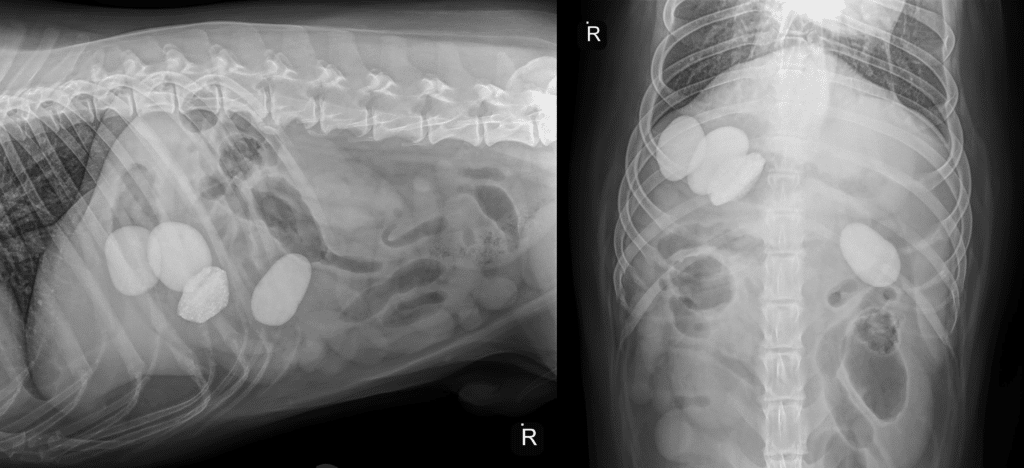

One of the best uses of x-rays is to diagnose a broken bone. Bone contains a lot of the mineral calcium, which readily shows up on x-rays. Similarly, rocks—composed of dense minerals—are easy to identify on x-ray, as you can see in the x-ray of an overly-curious dog’s stomach below.

Veterinarians also use x-rays to diagnose bladder stones, which are simply internal rocks.

An x-ray is a two-dimensional representation of a three-dimensional pet. To locate a structure or abnormality accurately you need more than one x-ray of the patient

For example, look at the x-rays of a dog who ate rocks. No question there are 4 rocks, and they look close together in the x-ray taken from side to side. But in the second x-ray, taken from top to bottom, you see three rocks together in the stomach and one in the intestine. Without both views, the surgeon would be looking in the wrong spot to find and remove the rocks.